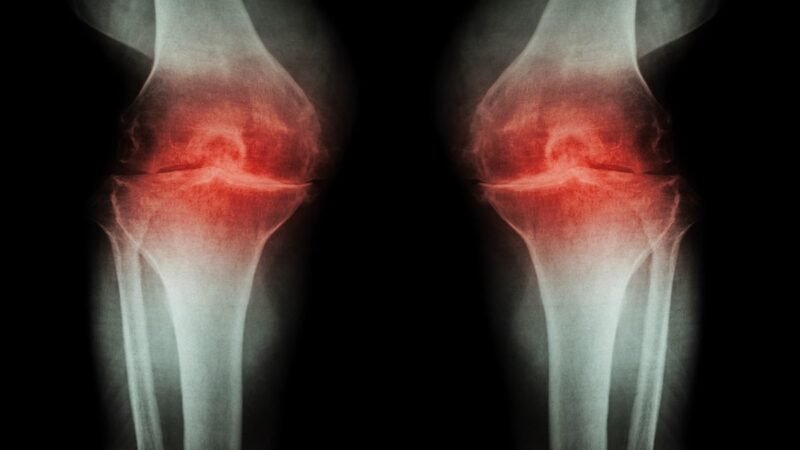

जोड़ों के लिए भी नुकसानदायक

स्ट्रेस और एंग्जायटी की वजह से शरीर के जोड़ भी कमजोर होते हैं। अत्यधिक स्ट्रेस बॉडी इंफ्लामेशन बढ़ाता है। आर्थराइटिस के मरीजों के लिए तो दिक्कत ज्यादा हो सकती है। तनाव से शारीरिक काम भी कम हो जाता है, जिससे तकलीफ बढ़ सकती है।